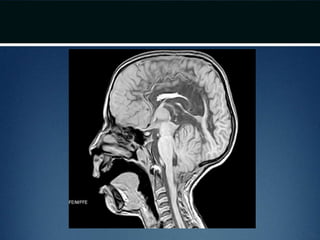

• MRI – Craniovertebral junction and entire

spinal cord

• 50-75% patients have syringomyeliasyrinx

• CT – bony abnormality; plain films for

evaluating stability issues

• Dynamic MRI (cine MRI) – for CSF flow

around the CVJ